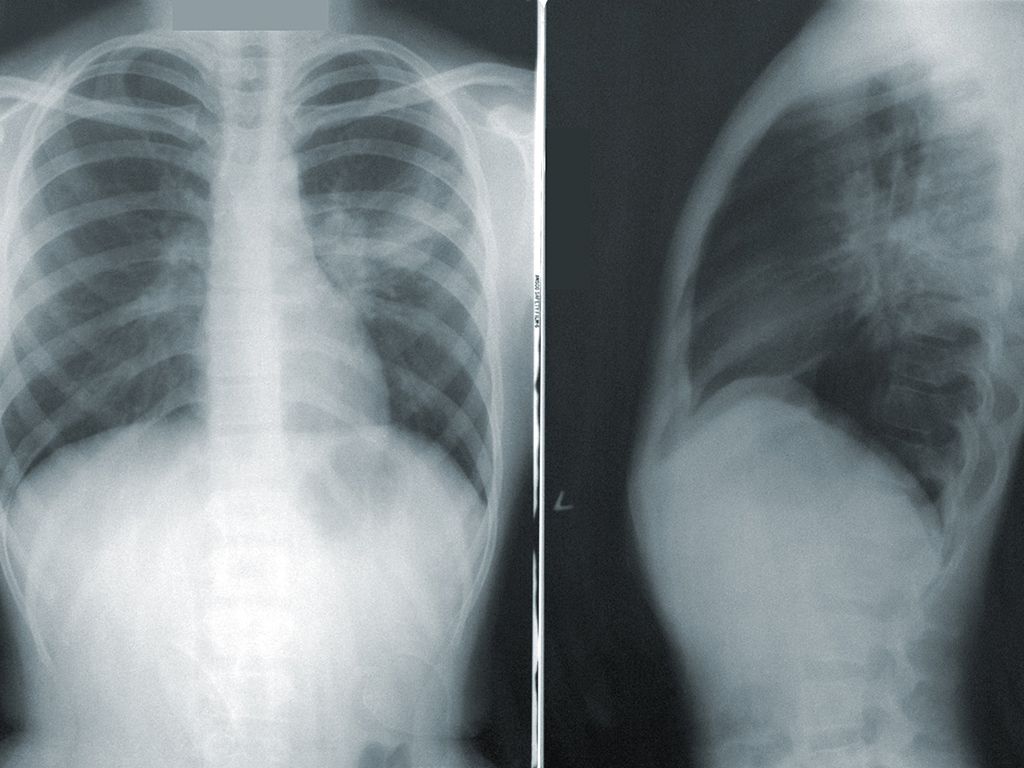

I Knew Something Was Wrong

I was the patient in this story. When I was between 7 and 9, I had my first port put in, which is an IV catheter attached to the main vessels in my heart. When I woke up, I knew something was wrong. My lungs were horrible already, but this was way worse. I couldn’t breathe and I was in so much pain.

The doctor, however, thought I was just being a kid and not handling the pain very well. My nurse knew me pretty well, though, and after me crying and struggling to breathe for a few hours, she convinced the doctor I didn’t normally act like that and that something was really wrong.

He ordered an X-ray and we found out that the surgeon had accidentally sliced my lung when he was putting the port in, and my lung had collapsed.